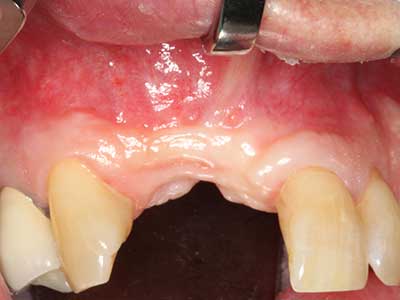

Indikation: Bone Splitting

Knochengewebe ist nicht nur rein mineralisch, sondern auch in wesentlichen Anteilen aus Kollagenfasern aufgebaut. Dies gewährleistet neben einer guten Druckfestigkeit eine gewisse Flexibilität, welche für die Durchführung von Augmentationen genutzt werden kann. Bei der klassischen Expansionsplastik im Sinne eines Bone Splittings wird der atrophierte Kieferkamm in seiner Längsachse gespalten und nach Erreichen einer ausreichenden Osteotomietiefe vorsichtig aufgedehnt (Abb. 13-16), idealerweise ohne den Kiefer wesentlich zu deperiostieren (Brugnami, Caiazzo et al. 2014, Stricker, Fleiner et al. 2014). Bewährt haben sich Schrauben- und Plattensysteme mit zunehmender Expansionsdistanz, um die beiden Knochenlamellen unterhalb der Bruchschwelle voneinander zu distanzieren. In der Regel werden Restknochenbreiten von mindestens 3-4 mm gefordert (Chiapasco, Zaniboni et al. 2006), um eine ausreichende Flexibilität und knöcherne Bedeckung der einzubringenden Implantate zu gewährleisten. Ggf. kann eine ein- oder beidseitige vertikale Entlastungsosteotomie die Flexibilität verbessern. Als Alternative zur klassischen Technik wurde eine Kombination mit weiteren augmentativen Techniken vor allem auf der bukkalen Seite beschrieben.

Mittels Piezosägen erfolgt die Anlage des Splittings besonders schonend und ohne wesentliche Dimensionsverluste, so dass sich keine signifikanten Unterschiede von Implantaten im gesplitteten Kiefer im Vergleich zum nicht defizitären Alveolarkamm gezeigt haben (Chiapasco, Zaniboni et al. 2006, Danza, Guidi et al. 2009). Gerade beim lokal begrenzten und tiefen Splitting ist jedoch stets auf eine ausreichende Wasserkühlung zu achten, um thermische Belastungen in den apikalen Osteotomiebereichen zu vermeiden.